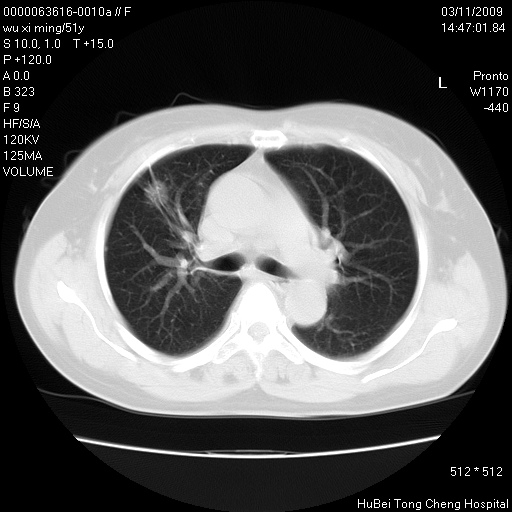

患者 女,51岁。因“胆囊炎,胆囊结石”,行常规术前胸部x线检查发现:右上肺结节病灶,建议行进一步检查。患者无咳嗽、咳痰及咯血等呼吸道症状,近期出现背部疼痛不适。

胸部ct轴位平扫(层厚10mm,螺距1.5,重建间隔10mm;部分层面:层厚3mm,螺距1.0,重建间隔3mm),图像如下:

1、周围型肺癌。(毛刺正、血管束集征,分叶。)

集束征,胸膜牽拉征,毛刺,淺分葉高度提示ca.

右肺周围型肺癌伴肺内转移及胸椎转移。已无手术机会。